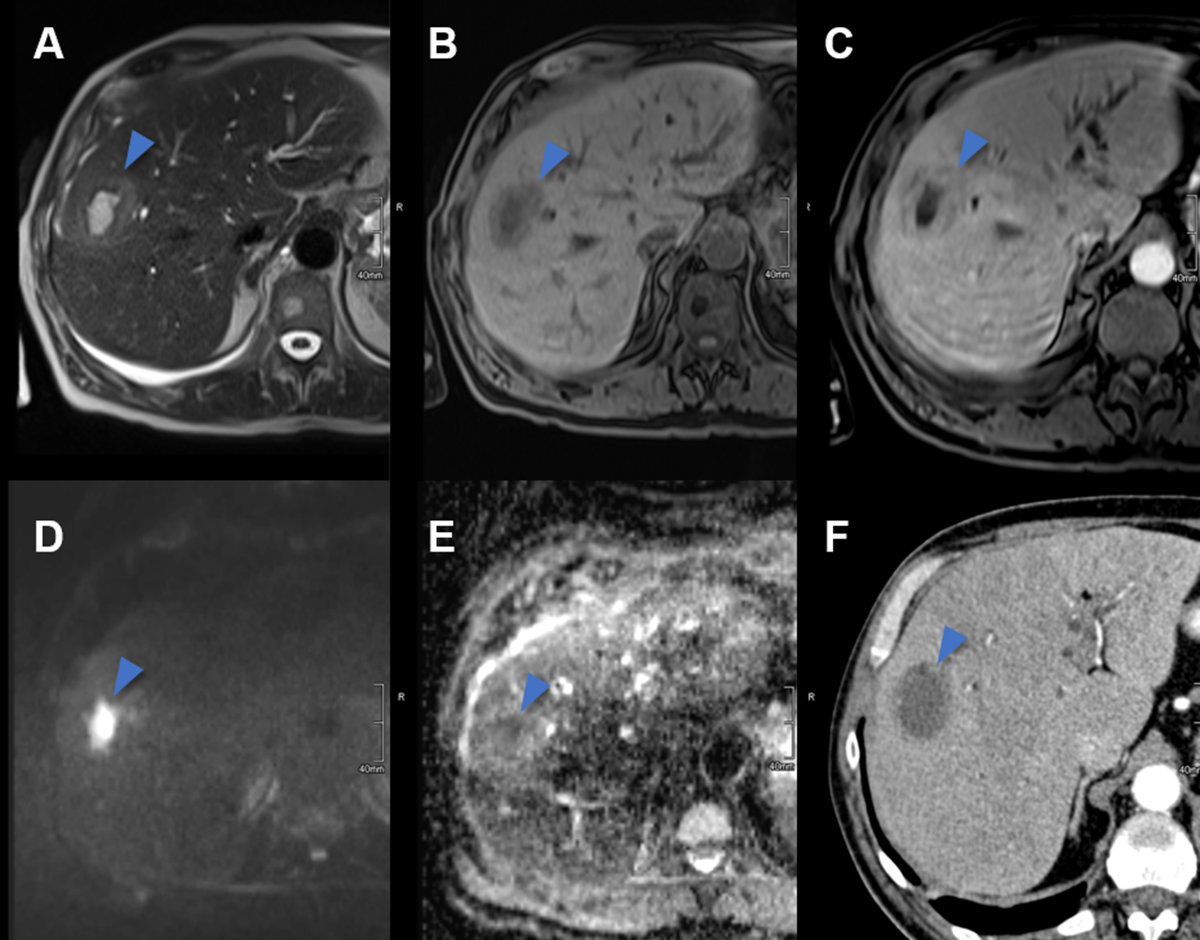

Figure 18Hepatocellular adenoma in MRI. MRI of a HNF-1a-activated hepatocellular adenoma in liver segment II (arrow) with A hyperintense signal on the T2w image, signal drop from B T1 weighted in- to C opposed-phase, D arterial enhancement persisting in E the portal venous phase and F due to lack of contrast metabolisation hypointense signal on hepatobiliary phase images.

On MRI images, inflammatory hepatocellular adenomas are hyperintense on T2w images and isointense or mildly hyperintense on T1w images with minimal or no signal drop-off on opposed-phase images. After the administration of gadolinium-based contrast material, inflammatory hepatocellular adenomas usually demonstrate avid arterial enhancement, which persists in the portal venous and delayed phases [58]. HNF-1α-inactivated hepatocellular adenomas are hyper- or isointense on T1w images, with typical diffuse signal drop-off on opposed phase due to intracellular fat [58].